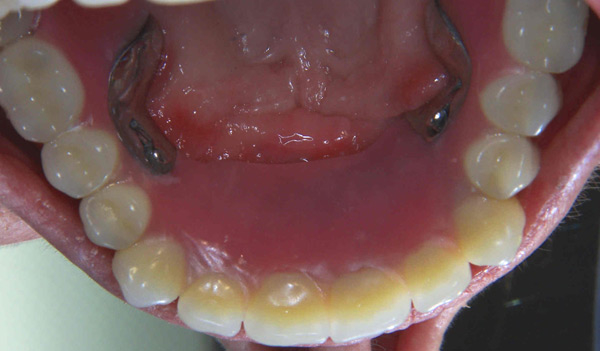

Problem: This patient had a series of problems that resulted with tooth loss. He also has a problem with sleep apnea. He wanted something fixed and stable.

Plan: Our plan… placed four implants on the lower with a fixed/hybrid prosthesis. Placed five on the upper arch with a titanium bar and snap attachments to allow a special one of the kind sleep apnea device.

He really likes his new smile and he gets a great nights rest as well.